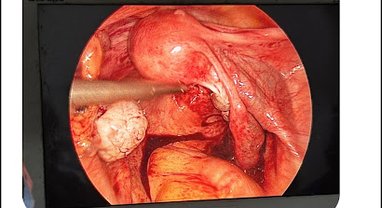

Recently done surgery at Aster Women Hospital, and I am extremely satisfied with the care we received. From the moment she was admitted, the doctors and nursing team made sure she felt safe, supported, and well-informed. Dr. Khushbu and Dr. Arjun explained everything clearly, and handled the procedure with great expertise. The nursing staff was like a cherry on top, kind, attentive, and always quick to respond to needs. The hospital environment was clean, organized, and reassuring, and the overall service exceeded my expectations. truly grateful for the excellent treatment and care at Aster Women Hospital. Highly recommended for anyone looking for dedicated and compassionate women’s healthcare! ~ Narendra P